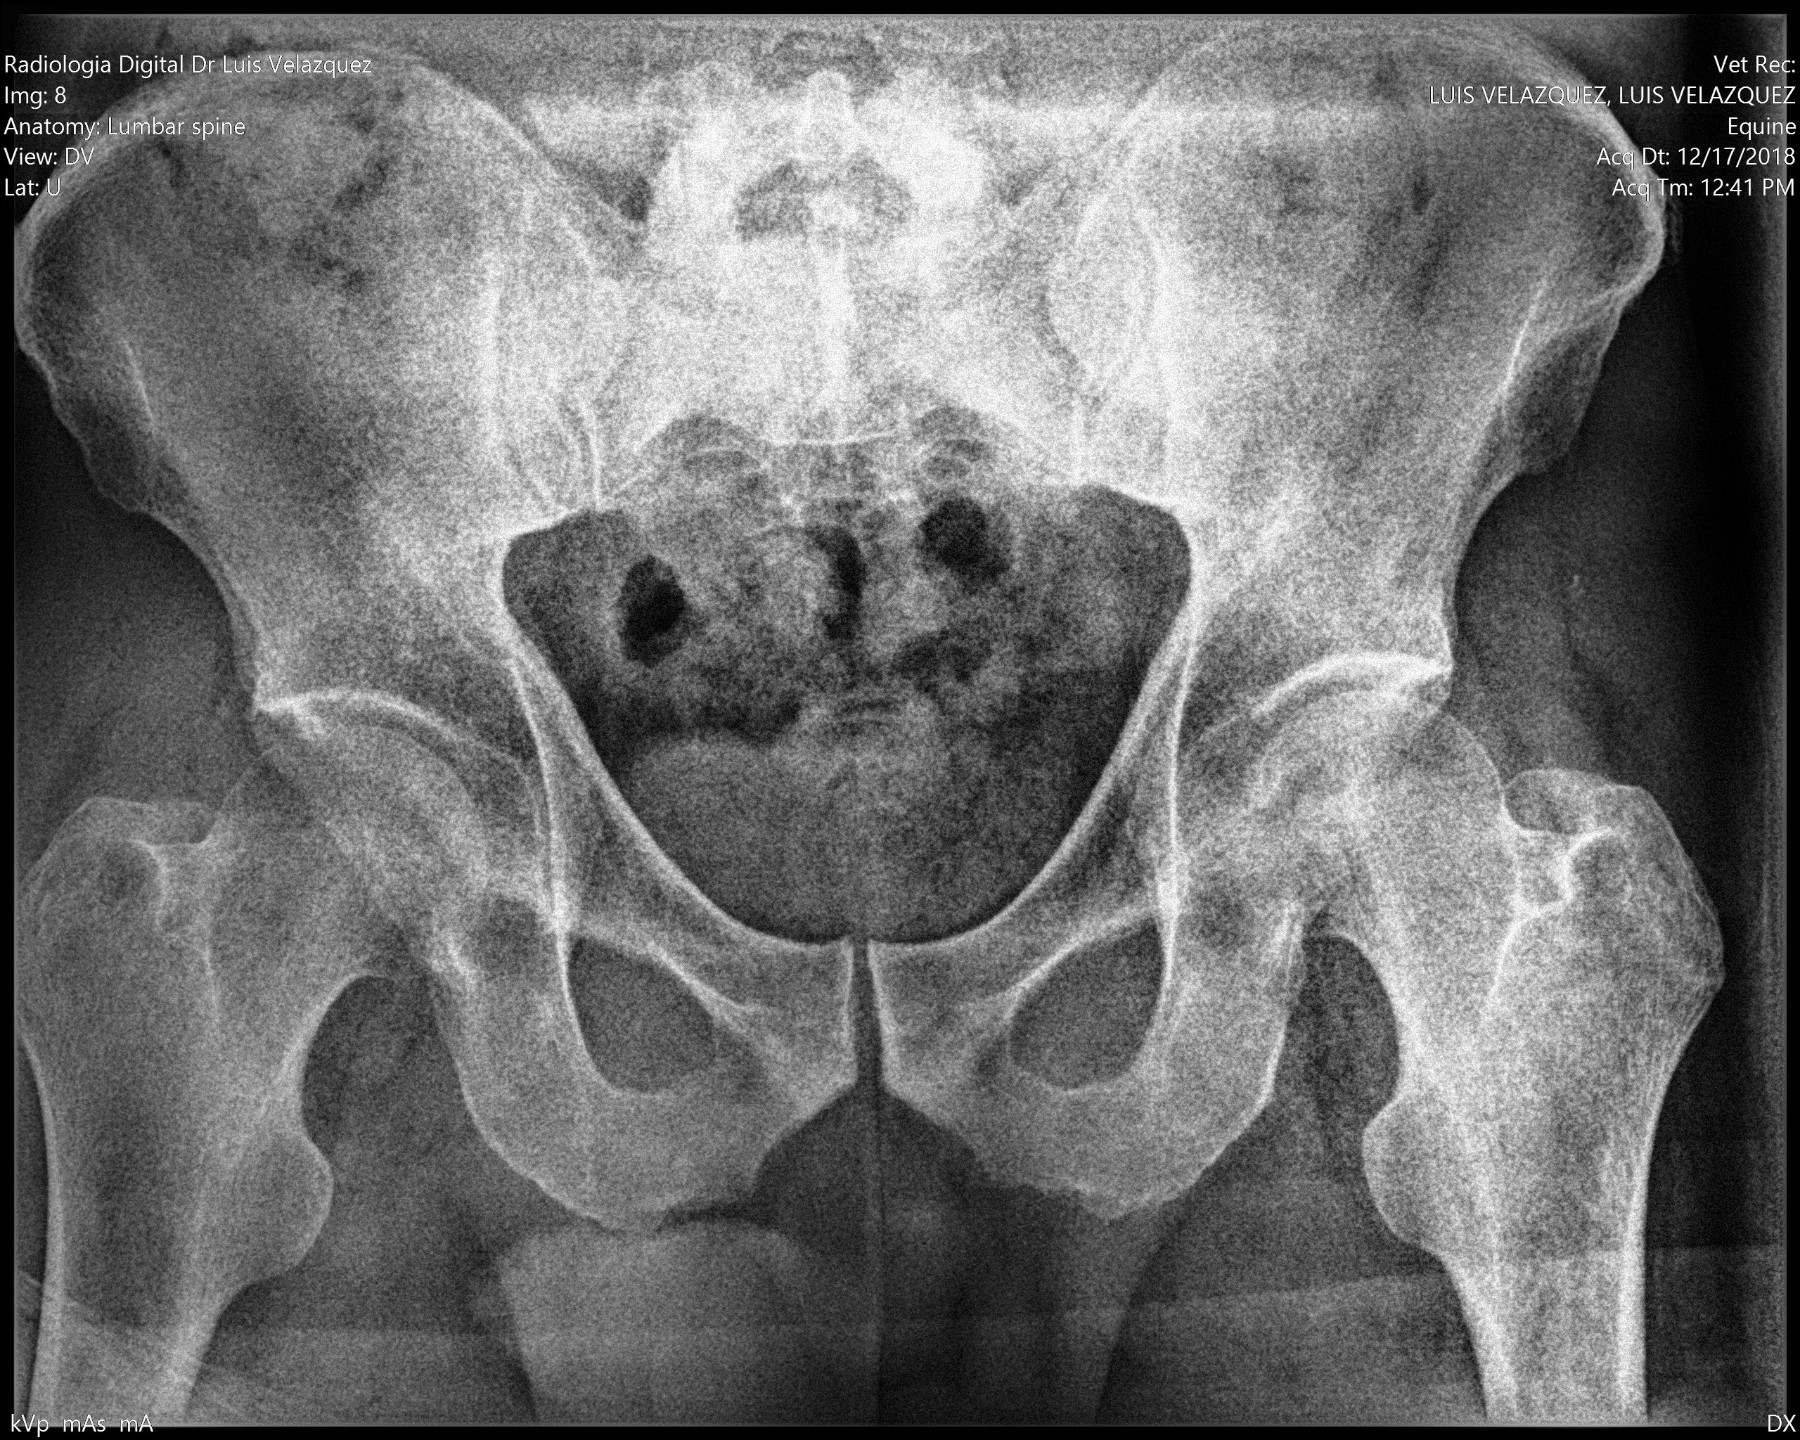

Radiología Digital como Herramienta Complementaria en el Dictamen de Bienes Muebles

Desde el descubrimiento de los rayos “X” y las placas radiográficas por Wilhelm Conrad Roentgen y su posterior difusión a través de la Asociación Físico médica de Wurzburg el 28 de diciembre de 1895, que fue la primera asociación que habló de los nuevos rayos que podían penetrar el cuerpo y fotografiar los huesos, ha habido muchos cambios tanto en la forma de obtener, procesar e incluso en la forma de visualizar, manejar y almacenar las placas radiográficas.